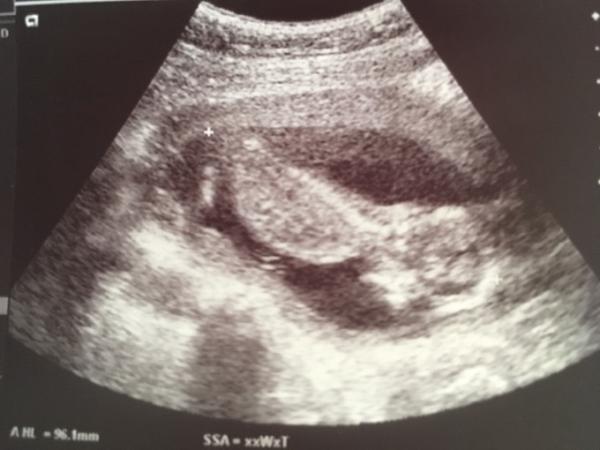

...die Zeit der Schwangerschaft geht schneller vorbei, als du denkst... Ich habe im Moment das Gefühl, dass gar nichts voran geht Der Bauch will noch nicht richtig wachsen...Nächster Termin ist erst in knapp 2 Wochen...Ich würde gerne schon die Bewegungen spüren... An manchen Tagen habe ich keine Ahnung, was ich noch so essen kann...Habe das Gefühl, dass es immer das gleiche gibt (was ja nicht stimmt)... Irgendwie ziehen sich die Wochen wie Gummi... Werde nach der nächsten Vorsorge mal nach einem Kurs schauen...vllt Yoga - oder Gymnastik... Wie verkürzt ihr euch die Zeit zwischen den einzelnen Etappen? Anbei noch ein Bild von der letzten Untersuchung bei 13+2

Bild zu Alle sagen immer... - Forum für April - Mamis